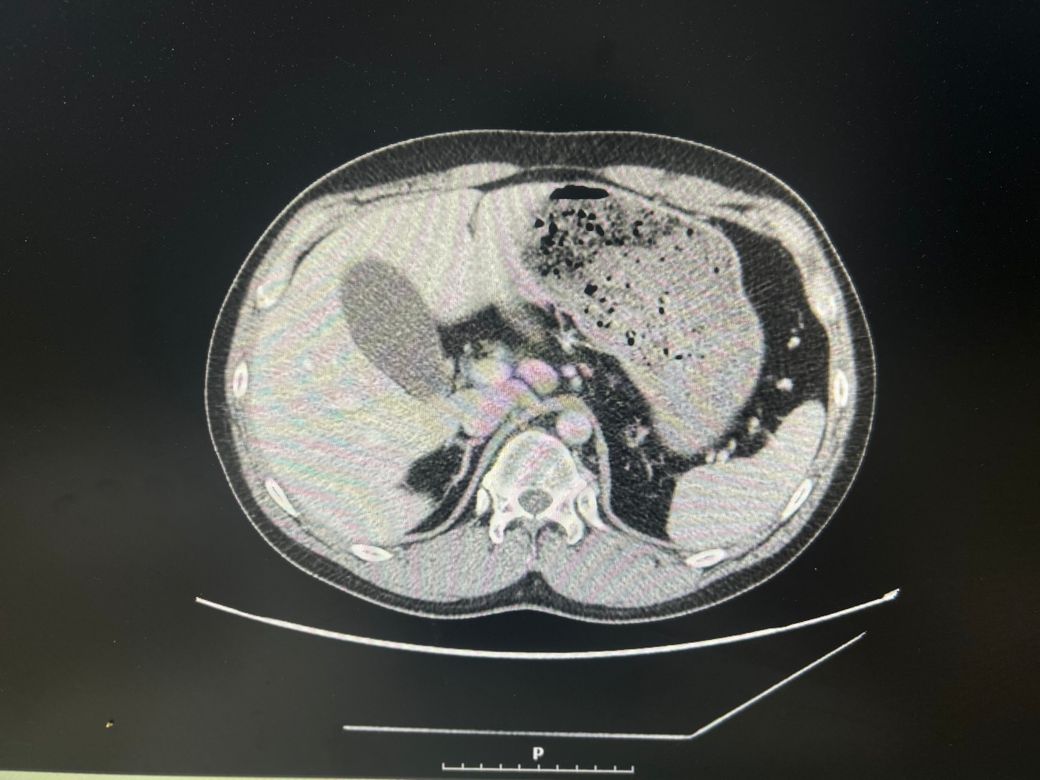

우상복부 통증(좌상복부 통증도 생김), 오른쪽 어깨에서 허리까지통증, 소화불량, 팽만감,답답함, 설사 증상이 있는데..... 담낭염이 맞을까요?

• 1번 째 사진

CT에서 담낭염은 담낭벽이 두꺼워보이고 벽이 조영증강되는데

환자분 자료의 경우 그런 소견이 뚜렷하게 보이지는 않는 것 같습니다.

• 애매합니다. 담낭의 크기가 다소 늘어나 보이긴 합니다만, 당남염을 강력하게 의심할만한 다른 소견들이 보이지는 않습니다. 가령 담낭의 벽이 두꺼워지거나 담낭 주변의 염증 소견, 담낭 목을 막고 있는 담석 등이 따로 관찰되거나 하지는 않기 때문에 담낭염을 강력하게 의심하기는 어려워 보입니다. 우상복부의 압통 및 머피징후 등의 신체검진 소견이 있다면 담낭염의 가능성을 고려해볼 수 있겠습니다만, 해당 CT 소견만으로는 판단하기 어렵습니다.

첨부해주신 CT 영상에는 담낭 주변에 두드러지는 염증소견이 관찰되지 않습니다. 다만 영상의 모든 단면을 확인한 것이 아니라서 담석증의 여부에 대해서는 확답드릴 수 없습니다. 증상이 지속되면 내과에서 진료를 받아보시는 것을 권해드립니다.